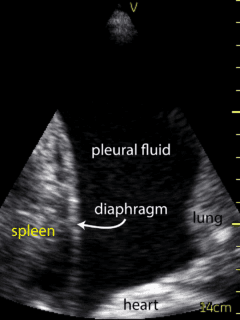

Ultrasound of the lung conducted by the Respirologist using a VScan device revealed a small amount of right pleural effusion and a moderate sized left pleural effusion. The ultrasound was used to landmark the site of needle insertion for thoracentesis (Figure 2, Video 2), at the 8th intercostal space, roughly 10 cm from the spine. Following anesthesia with lidocaine, the thoracentesis catheter was inserted along the same angle. A total of 500 ml was drained from the pleural space. The procedure was terminated as the patient began to experience some chest discomfort.  Following thoracentesis, ultrasound was repeated and there was no significant remaining fluid.  Sliding lung/pleura was visualized. The procedure was otherwise well tolerated. Fluid was sent for routine analysis, as well as cytology, flow cytometry, and cultures.